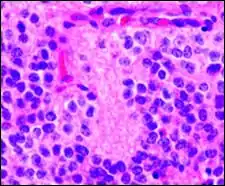

Micrograph of perivascular pseudorosettes

A perivascular pseudorosette consists of a spoke-wheel arrangement of cells with tapered cellular processes radiates around a wall of a centrally placed vessel. The modifier “pseudo” differentiates this pattern from the Homer Wright and Flexner-Wintersteiner rosettes, perhaps because the central structure is not actually formed by the tumor itself, but instead represents a native, non-neoplastic element. Also, some early investigators argued about the definition of a central lumen, choosing “pseudo” to indicate that the hub was not a true lumen but contained structures. Nevertheless, this pattern remains extremely diagnostically useful and the modifier unnecessarily leads to confusion. Perivascular pseudorosettes are encountered in most ependymomas regardless of grade or variant. As such, they are significantly more sensitive for the diagnosis of ependymomas than true ependymal rosettes. Unfortunately, perivascular pseudorosettes are also less specific in that they are also encountered in medulloblastomas, PNETs, central neurocytomas, and less often in glioblastomas, and a rare pediatric tumor, monomorphous pilomyxoid astrocytomas.[2]

Perivascular pseudorosette